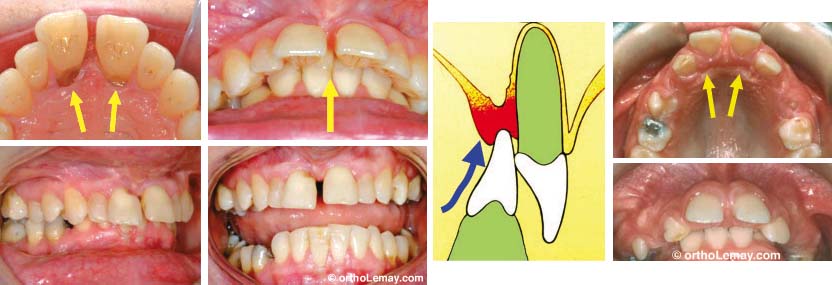

En présence d’un surplomb antérieur vertical excessif (overbite), les dents inférieures peuvent mordre dans la muqueuse du palais et l’endommager en causant du déchaussement et éventuellement une perte osseuse. Un phénomène similaire, l’affaissement postérieur de l’occlusion, peut se produire lors de la perte de dents postérieures qui servent de “fondation” à l’occlusion. La perte des dents cause des déplacements antérieurs, des espaces, etc. Pour en savoir plus sur ce sujet, suivez le lien ci-dessous.